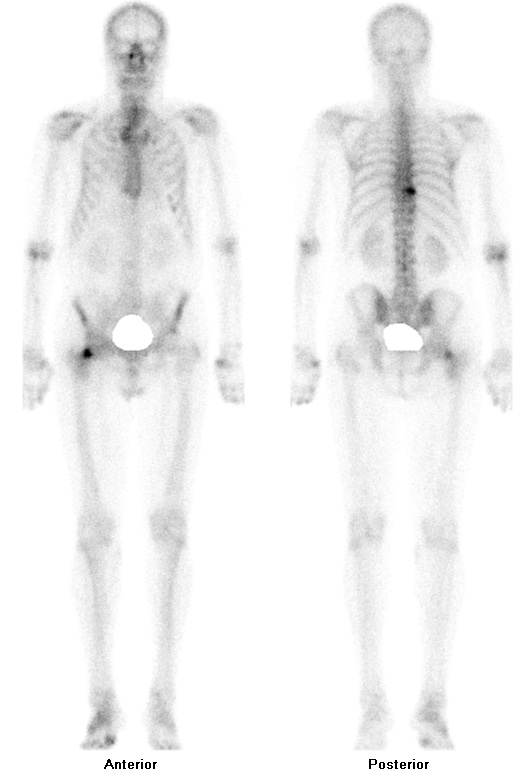

Гиперфиксация рфп при пэт кт

Гиперфиксация рфп при пэт кт 140 фото